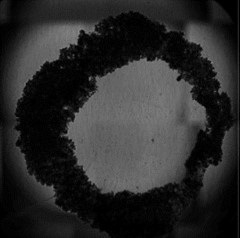

The assay we have developed is a circle with a hole in the middle, and over time, this hole is closed, much like a wound would close. When people think of a wound, they generally think of epithelial cells, fibroblasts and the other cell types that close a wound.

That is where magnetic 3D cell culture comes in. We use magnetic fields as a surrogate for cell attachment in 2D. We decorate the cells with magnetic nanoparticles – we call this the NanoShuttle – and then we use a ring magnet to guide the cells into the shape of a ring with a hole inside – a toroid type of geometry.

We can then observe the cells closing as a three-dimension structure. The magnetic field enables us to manipulate the cells, position these and create a shape that we can follow.

High throughput is also important, so we used a 384 well system with small ring magnets under each well to generate these wound-like structures. Cells can rapidly regenerate these ring patterns, and we can image these over time to get quantitative data regarding the wound culture.

Fig. 1: (Left) A 96-well plate placed on the CytoSMART® Omni inside a humified incubator. (Right) 3D ring construct representing a dermal wound.